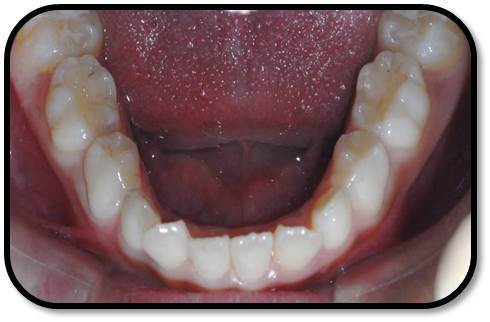

检查: 右上1牙冠略宽大,舌侧见粗大的畸形舌尖,叩痛(++),松Ⅰ°,唇侧牙龈红肿前庭沟膨隆扪痛,挤压唇侧龈缘溢脓,冷热测无反应,右侧上下1侧方颌,正中颌颌创伤。 X线:右上1发育7-8期,根管平行状,根尖孔宽大,约5-6mm宽,根尖周低密度影。髓腔根管宽大内见倒置牙影像,倒置牙可见髓腔。 余牙未见异常 6均已萌出建颌